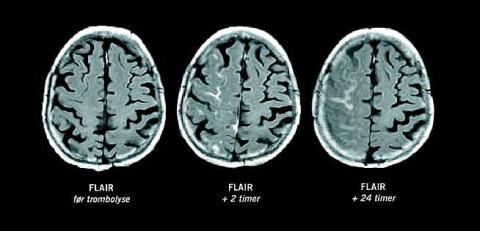

En 68-årig kvinde fik foretaget hjerneskanning med magnetisk resonans (MR) 135 minutter efter debut af venstresidig hemiparese og hypæstesi. MR-angiografi viste okklusion af en forgrening af højre arteria cerebri media, og diffusions-vægtet MR demonstrerede et tilsvarende parietalt infarkt. Intravenøs trombolytisk behandling blev påbegyndt 176 minutter efter symptomdebut. To timer senere var patientens kliniske tilstand normaliseret, og opfølgende MR-angiografi viste komplet rekanalisering. På fluid-attenuated inversion recovery (FLAIR)-billederne sås nu diffus opladning i cerebrospinalvæsken over hele højre hjernehalvdel.

Rekanalisering af et okkluderet cerebralt kar - og dermed reperfusion af hjernevæv - kan forårsage hæmoragisk transformation som følge af forudgående iskæmisk beskadigelse af blod-hjerne-barrieren. Gadoliniumholdigt kontraststof, som indgives intravenøst ved perfusions-vægtet MR, passerer ikke en intakt blod-hjerne-barriere. Gadolinium i cerebrospinalvæsken, som altså er en markør for beskadigelse af blod-hjerne-barrieren, fremstår hyperintenst på FLAIR og er en uafhængig prædiktor for hæmoragisk transformation [1].

Opfølgende skanninger viste ikke blødning i dette tilfælde.